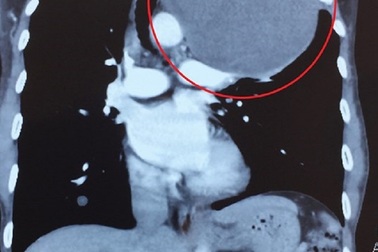

Cần Thơ: Phẫu thuật thành công khối u trung thất nặng 4kg, đè xẹp phổiNgày 4/4/2019 nguồn tin từ Bệnh viện Đa khoa Trung ương Cần Thơ cho biết, các bác sĩ của bệnh viện này vừa phẫu thuật thành công cho bệnh nhân có khối u trung thất với trọng lượng lên đến 4kg, đè xẹp phổi.

Nam bệnh nhân mang khối u to như quả bóng trong lồng ngựcNhập viện trong tình trạng đau nhiều ở đỉnh lồng ngực trái và vùng vai, cổ… người đàn ông 54 tuổi được xác định bị khối u trung thất khổng lồ. Các bác sĩ đã tiến hành phẫu thuật mở lồng ngực bóc tách thành công khối u to như quả bóng cho người bệnh.